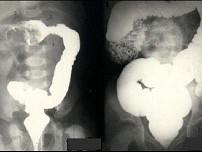

问题 女,2岁半,突然哭闹3小时,急性面容,腹部触诊上腹区似可扪及包块,行钡灌肠检查,如图所示,最可能的诊断为?(?)

选项 A.肠套叠 B.先天性巨结肠 C.结肠扭转 D.结肠炎 E.结肠癌

答案 A